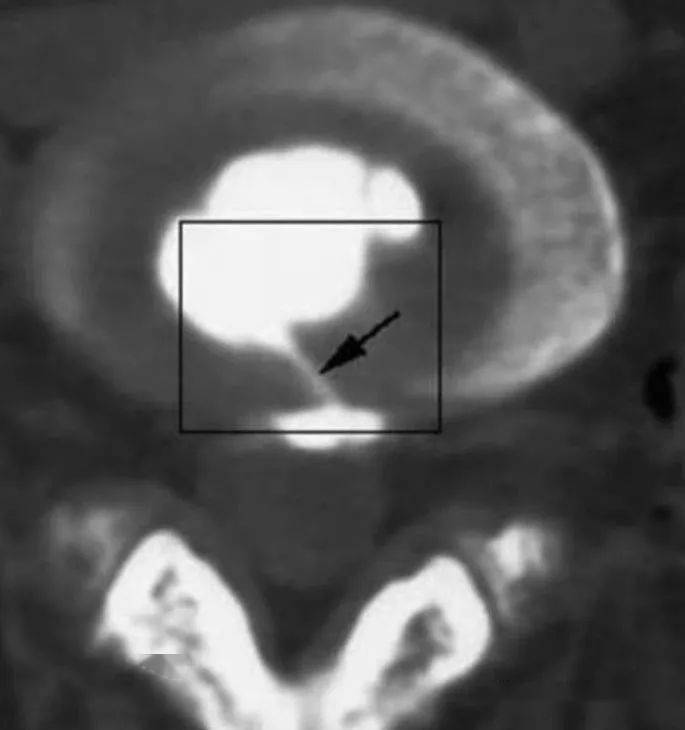

L3-4椎间盘后缘可见点状高信号区(红色箭头所指处)

红色箭头所指的异常信号区是是什么呢?平时工作中大家有没有遇到这种情况,你会不会忽略这个异常信号?有没有想过这个椎间盘后缘高信号区是引起患者腰疼的重要因素呢?下面为大家重点介绍。

影像表现主要在T2矢状位及T2横断位可见椎间盘前缘或后缘可见高信号区;

L3-4椎间盘后缘HIZ

图为椎间盘造影术后CT平扫所显示破裂的纤维环(箭头所指地方为纤维环破裂处),且造影剂流经破裂口至HIZ高信号区。(Peng B. Spine 2006;31(5): 560-66)